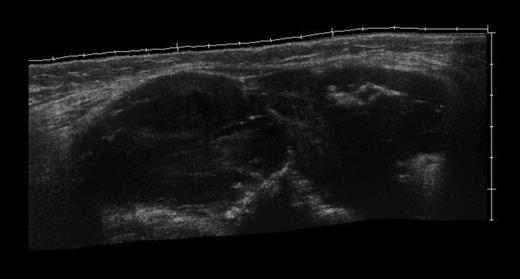

The MRI scan of the right knee (Figs 2 and 3) with gadolinium-enhancement showed a large mass lesion in the posterior aspect of the right knee extending into the popliteal fossa and into the upper third of the right leg having appearance of bursal pathology. Post gadolinium images showed evidence of circumferential rim enhancement but no internal enhancement indicating the presence of a fluid filled lesion. The mass (Figs 4 and 5) measured ∼8.39 × 6.14 × 12.72 cm and was seen between semimembranosus and biceps femoris muscles. There was no evidence of any infiltration of either the sciatic nerve or the popliteal vessels. A likely diagnosis of complicated synovial cyst with a differential diagnosis of haematoma was reported and a provisional diagnosis of Baker's cyst was established.

T1-weighted MRI image showing mass occupying whole of posterior aspect of knee extending to proximal portion of the leg.